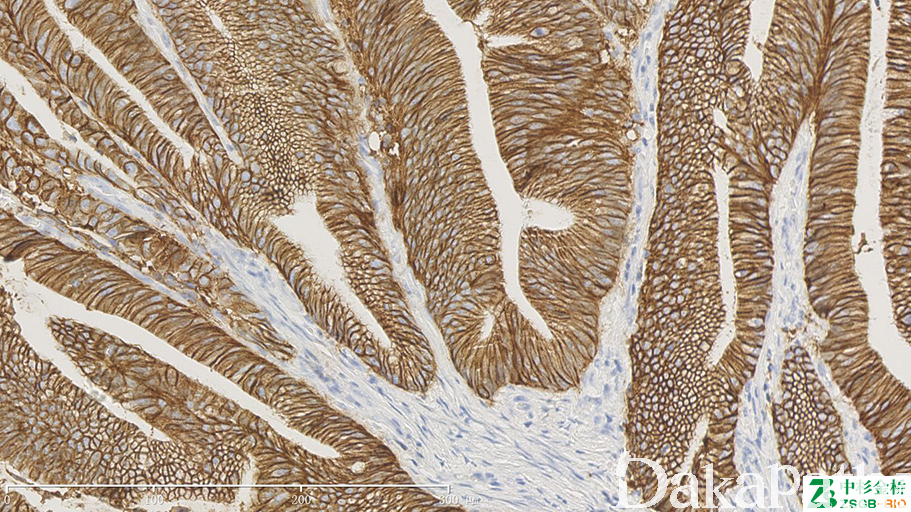

EpCAM

信号定位: 胞质、胞膜

几乎全部阳性(≥95%的病例阳性): 结直肠腺癌、前列腺腺泡性癌、皮肤基底细胞癌、类癌、甲状腺滤泡性腺瘤、甲状腺滤泡性癌、甲状腺乳头状癌、淋巴上皮癌、肺大细胞癌、涎腺腺泡细胞癌、黏液表皮样癌、卵巢无性细胞瘤、卵巢黏液性癌、外阴基底细胞癌、食管腺癌、甲状旁腺腺瘤、嗅神经母细胞瘤、子宫内膜腺癌、乳腺伴大汗腺分化的癌、甲状腺腺瘤、腹膜原发性腺癌、小肠腺癌、肝内胆管细胞癌、宫颈腺癌,非特指型、卵巢浆液性癌、甲状旁腺癌、胃肝样腺癌